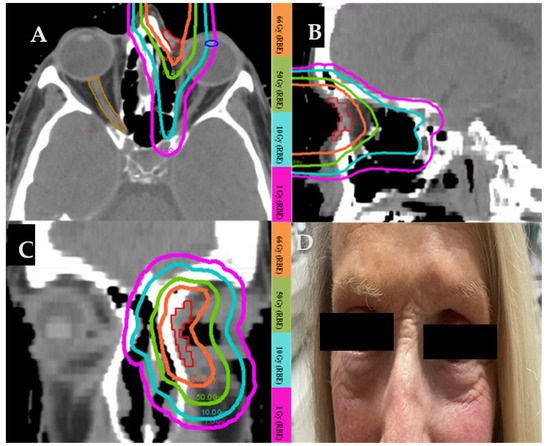

3.4.2. Case 2 (Figure 2)

A 63-year-old female with biopsy-proven recurrent basal cell carcinoma on the left medial canthus with post-septal involvement. Surgery would require orbital exenteration of the normal functioning eye. She underwent definitive proton beam therapy with a total dose of 66 Gy(RBE). Figure 2A–C show the axial, sagittal, and coronal views of dose distribution of this patient’s proton plan. The photograph (Figure 2D) was taken 14 years after the completion of protons. There was no evidence of a recurrence. The patient developed mild skin hypopigmentation in the irradiated area and loss of the medial aspect of the left eyebrow.

Figure 2. Proton treatment plan in axial (A), sagittal (B), and coronal (C) plane. (D) Picture of the treated area in the left medial canthus taken 14 years after the completion of proton therapy.